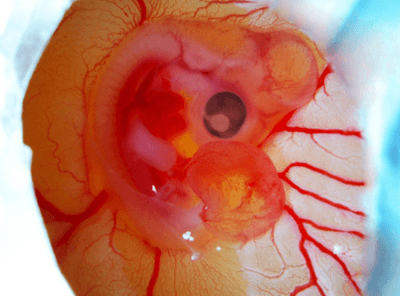

The rest of this article is behind a paywall. Please sign in or subscribe to access the full content.Scientists at Leiden University in the Netherlands investigated how polystyrene nanoplastics were impacting the development of chick embryos. To their alarm, they found that the human-made particles were linked to malformations in the heart, eyes, and nervous system.

“We see malformations in the nervous system, heart, eyes, and other parts of the face,” Meiru Wang, lead study author at the Institute of Biology Leiden, said in a statement.

The problem is down to how nanoplastics affect neural crest cells, stem cells that are formed in the very early development of all vertebrates. The neural crest cells start in what will become the spinal cord, before migrating to help form other parts of the nervous system, as well as several vital organs, such as the arteries, heart, and face.

The study showed that nanoplastics “passively target” the embryonic neural crest cells, sparking a chain reaction that disrupts how those cells migrate and develop.